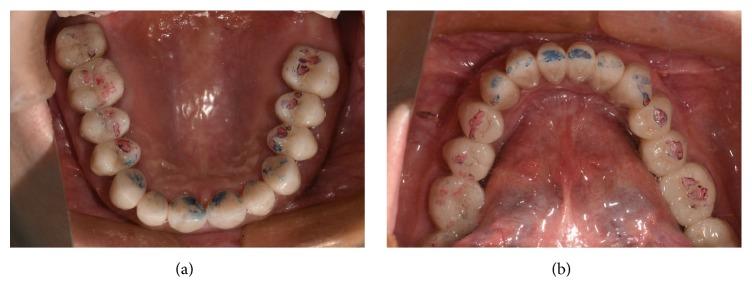

重度磨损牙合并前牙深覆(牙合)的固定修复方案

Full mouth reconstruction is one of the most effective methods to restore severe worn teeth that have suffered reduced vertical dimension. Although the use of the overlay splint restoration for a trial period allowing the patient to adapt to an increased vertical dimension is the recognized method, the specific protocol from the transitional splint to the fixed reconstruction is yet to be established. This case report describes a 50-year-old female patient who has severely worn teeth combined with an anterior deep bite and chewing pain. The protocol of the treatment process is described.

全口重建是恢复垂直距离降低的严重磨损牙齿的最有效方法之一。尽管使用覆盖式夹板修复进行一段时间的试验,让患者适应增加的垂直距离是公认的方法,但从过渡性夹板到固定重建的具体方案尚未确立。本病例报告描述了一名50岁女性患者,其牙齿严重磨损,伴有前牙深覆合和咀嚼疼痛。文中描述了治疗过程的方案。